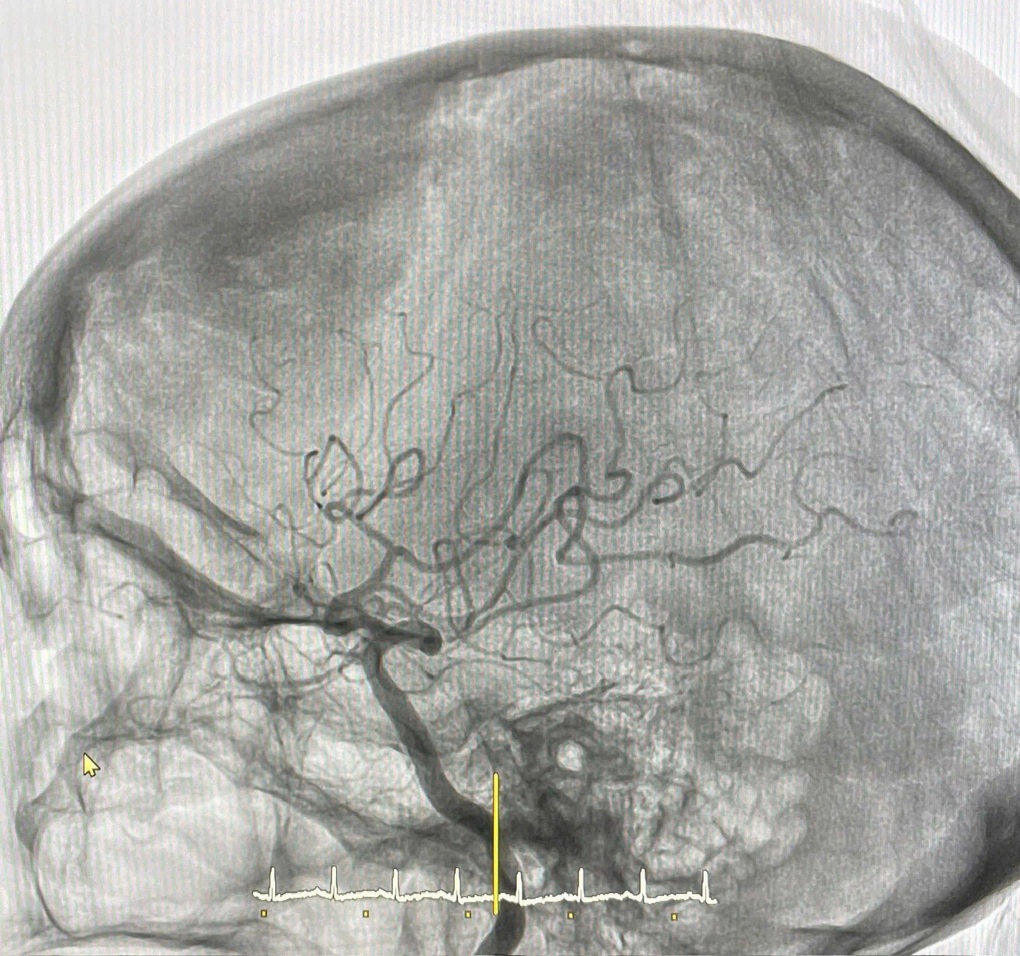

Kết quả cho thấy huyết khối đã gây tắc hoàn toàn động mạch não giữa phải đoạn M1.

Ê-kíp quyết định thực hiện thủ thuật hút huyết khối cơ học. Toàn bộ quá trình diễn ra thuận lợi, mạch được tái thông hoàn toàn và dòng chảy sau vị trí tắc được khôi phục, tạo điều kiện tối ưu cho mô não còn sống có cơ hội hồi phục.

Ảnh chụp não của bệnh nhân (Ảnh: Bệnh viện cung cấp).